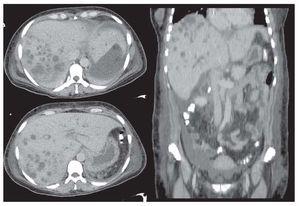

En todos los casos y después de una evaluación radiológica cuidadosa (Figuras 1 y 2), se determinó la necesidad de resección hepática de acuerdo con los siguientes criterios: a) presencia de colangitis refractaria a tratamiento médico con dilatación ductal segmentaria y/o abscesos colangíticos, b) falla en la resolución mediante manejo radiológico, c) falla transoperatoria para obtener un conducto adecuado para construir la anastomosis.

Figura 2. Colangiografía percutánea que demuestra dilatación de la vía biliar y abscesos colangíticos.